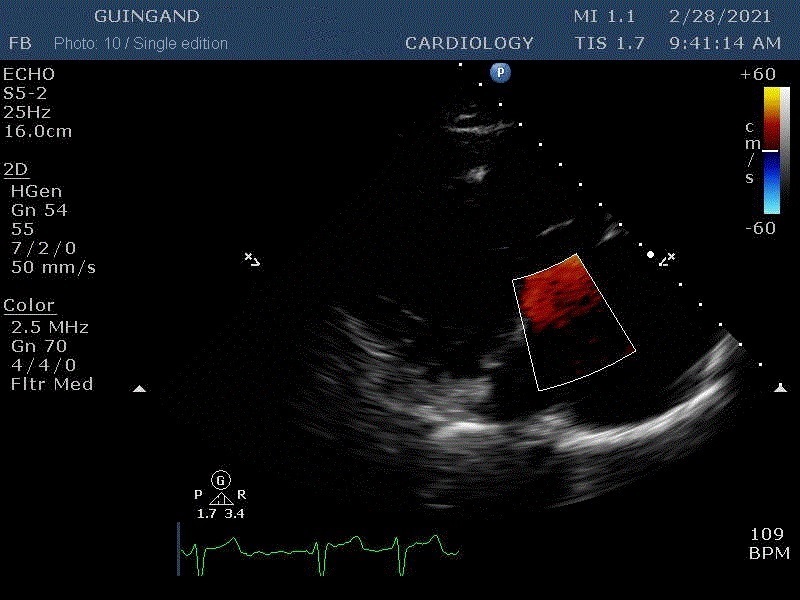

"Beats of my heart " NFT video

The very first heartbeat NFT to be sold in a marketplace The heart is the main vital organ of the human body. The expression “Put your heart into it” means to do something with sincere effort and passion. Guingand puts so much heart into everything he does — his life, his work, his relationships with others — that he has weakened his heart.

These are the first Cardiology NFTs for sale on a marketplace.

37 unique photos of the artist's most recent echocardiogram.

“Art is inside of us too.”